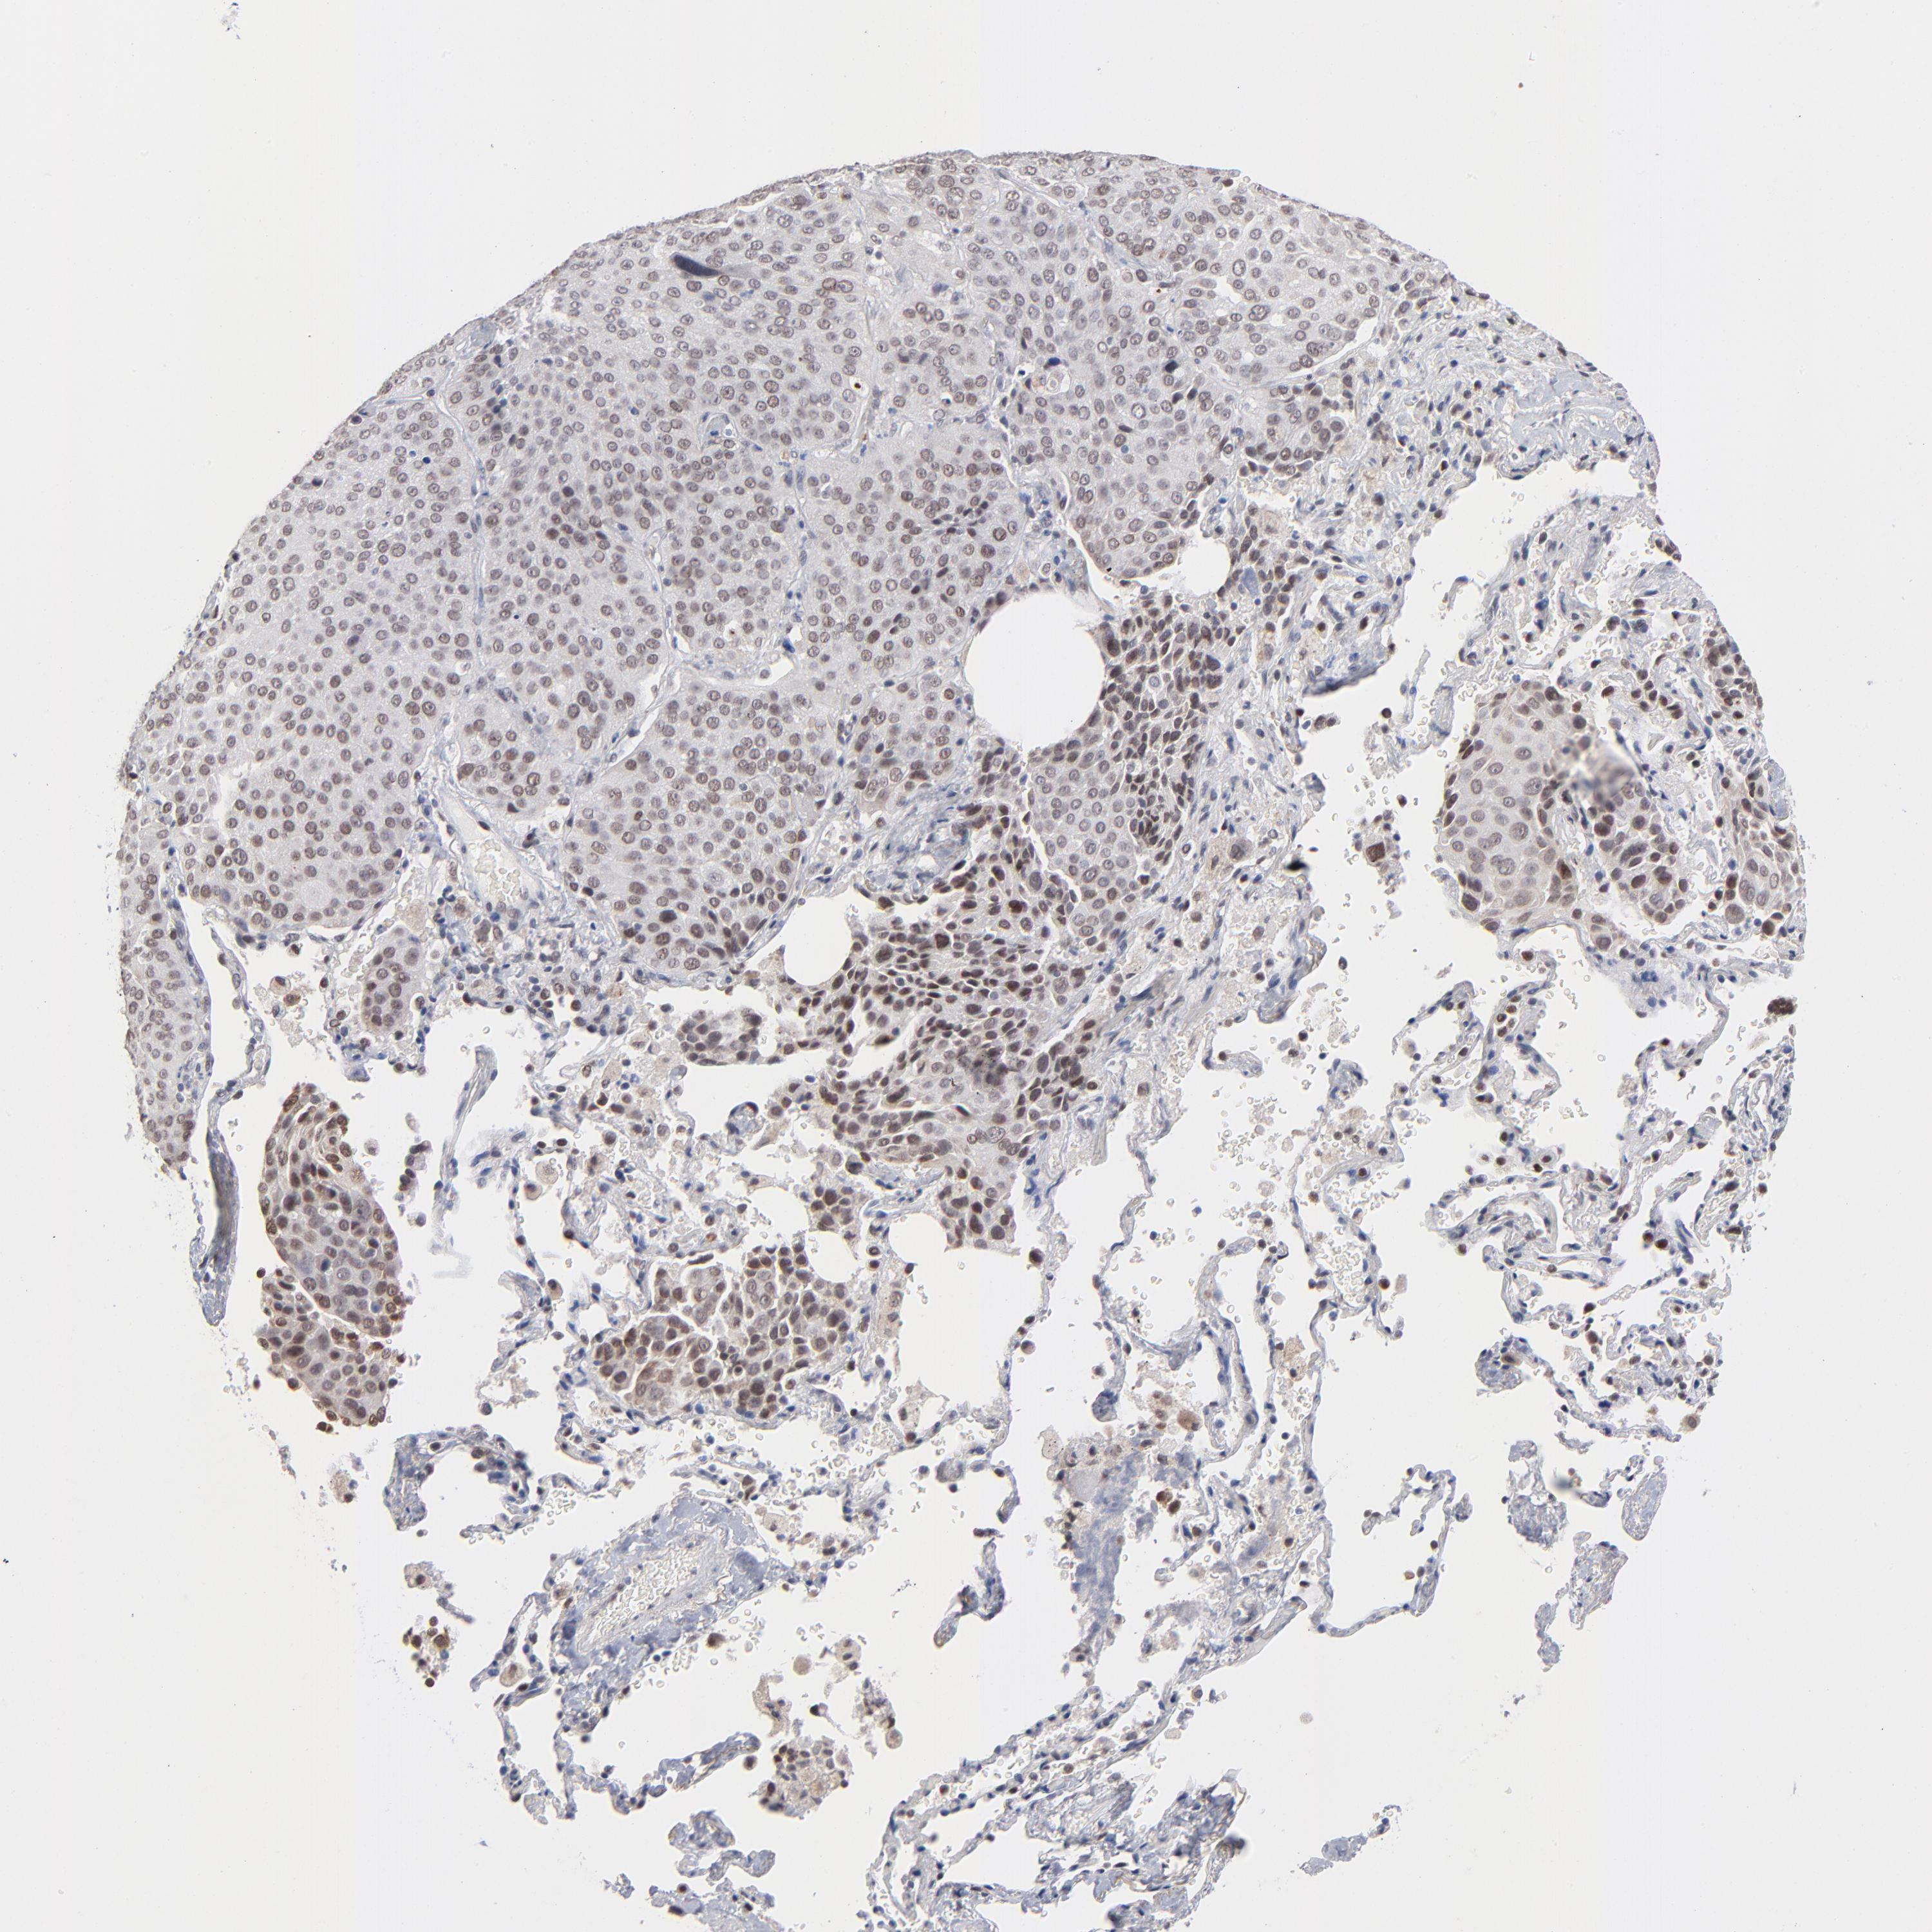

CANCER LUNG CANCER Show tissue menu

MBIP is potential prognostic, high expression is favorable in Lung Adenocarcinoma (TCGA)

MBIP is not prognostic in Lung Adenocarcinoma (validation)

MBIP is not prognostic in Lung Squamous Cell Carcinoma (TCGA)